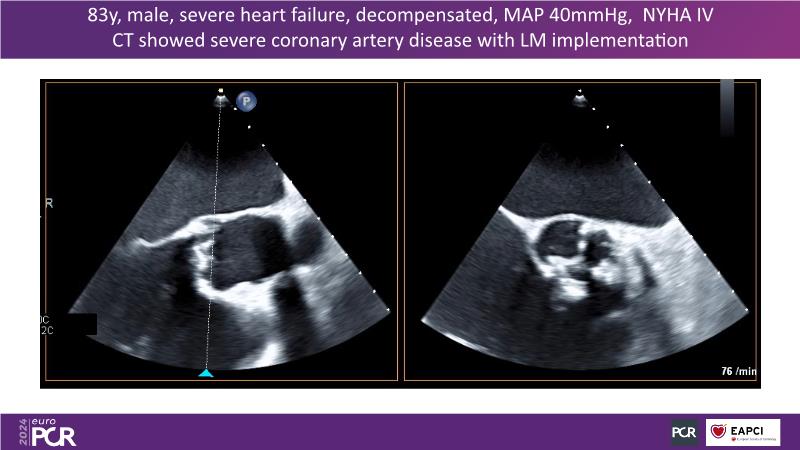

This session is essential for those looking to analyze and discuss the findings of the DanGer shock randomized trial, explore the latest evidence in the ACS field such as Horizon, and implement evidence-based practices in peri-procedural planning, execution, drug administration, and weaning strategies to optimize outcomes in acute myocardial infarction complicated by cardiogenic shock, since the session presents the latest data on ECLS and Impella, compares both in shock management, and offers insights on improving survival rates in shock patients, including the latest data on revascularization completeness with percutaneous ventricular assist devices versus IABP.

- To learn the latest data on ECLS, Impella and comparison of both in shock